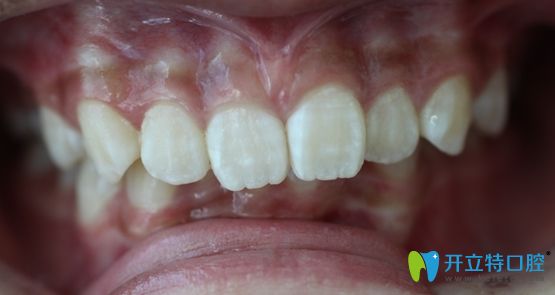

<深覆合加深覆蓋的牙齒“造型”>

大家誤噴哦,雖然這牙齒確實(shí)有點(diǎn)“一言難盡”........,重點(diǎn)是,影響咬合更影響美觀。

因?yàn)椋@種類型的牙齒通常都伴有上牙唇傾的狀況,而且大多側(cè)面突出(也就是凸嘴),有些還會(huì)出現(xiàn)發(fā)音異常,口呼吸等癥狀。